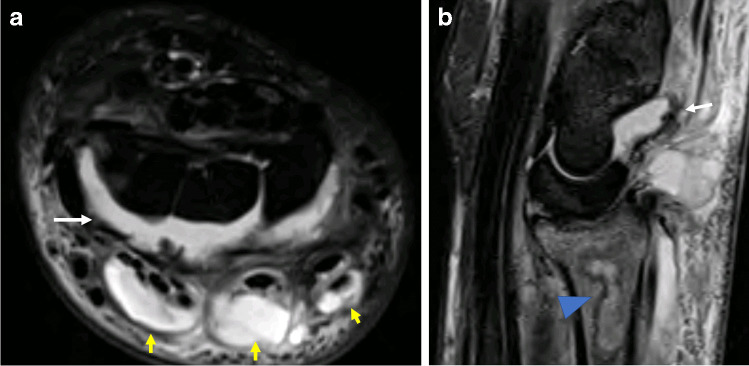

Fig. 1.

MRI of the right wrist in a 45-year-old man who presented with severe wrist pain, erythema and swelling 5 days after a fluoroscopic-guided wrist corticosteroid injection. Joint aspiration subsequently confirmed septic arthritis. Axial (a) and sagittal (b) STIR images of the right wrist demonstrate large radiocarpal and intercarpal effusions (white arrow), with marked changes of multifocal extensor tenosynovitis (yellow arrows). There is geographic signal abnormality in the distal radius in (b) consistent with osteomyelitis (arrowhead)

Fig. 2.

MRI of the left shoulder in a 65-year-old woman who presented with shoulder pain and fever 1 week after an ultrasound-guided acromioclavicular joint corticosteroid injection. Joint aspiration subsequently confirmed septic arthritis. Coronal (a) and sagittal (b) STIR images of the left shoulder demonstrate florid bone oedema spanning the acromioclavicular joint (white arrows), with marked periarticular soft tissue and subcutaneous oedema (arrowhead)